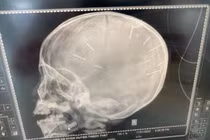

Ông nội bé 3 tuổi nghi bị bạo hành: "Tôi mong cháu vượt sống làm người, đời không thể ngắn ngủi được" - Ảnh 5.

Hình ảnh chụp X-quang hộp sọ của bệnh nhi. Ảnh: Đ.X.

Theo ông Kiên, Bệnh viện Đa khoa Xanh Pôn đã tiến hành chụp cắt lớp dựng hình, nhận thấy có những hình ảnh giống những đinh gỗ ở sọ và tổ chức não, tổng cộng 9 cái.